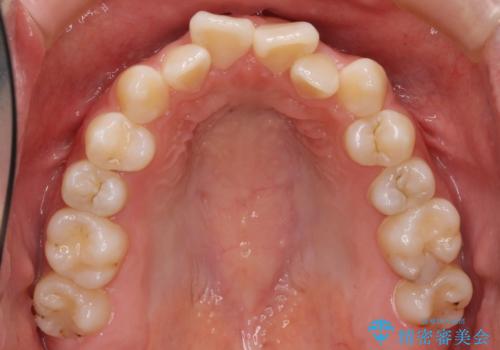

受け口 親知らずを取り込む矯正治療

- 高校生で来院。受け口が主訴でした。

下の小臼歯を抜歯しましたが、その代わり下の親知らずを残して咬ませたので、歯の数は変わっていません。